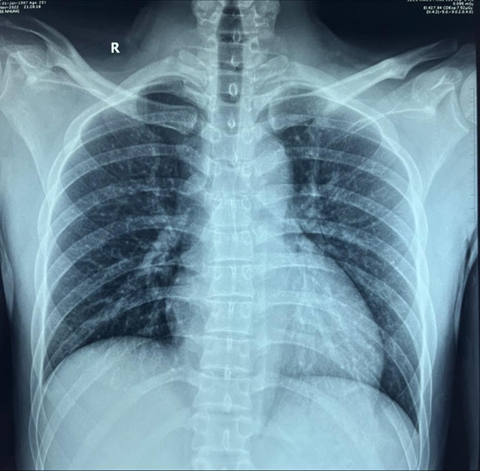

negative. His ecg (figure 1) demonstrated diffuse concave-upward

st-segment elevation and pr-segment depression, st-segment depression in avr or

v1. The patient’s chest x-ray (figure 2) showed an normal heart. Given

stage i (figure 1). Chest x-ray is usually normal in patients with

pericarditis and minimal effusion. However, when a large amount of effusion is

present (200- 250 ml), a chest x-ray will reveal a flask-shaped, enlarged

cardiac silhouette, and a possible left-sided pleural effusion7. The chest x-ray taken of our patient

demonstrated an normal cardiac silhouette. In this case, an echocardiogram

Figure 2. Chest xray showed normal